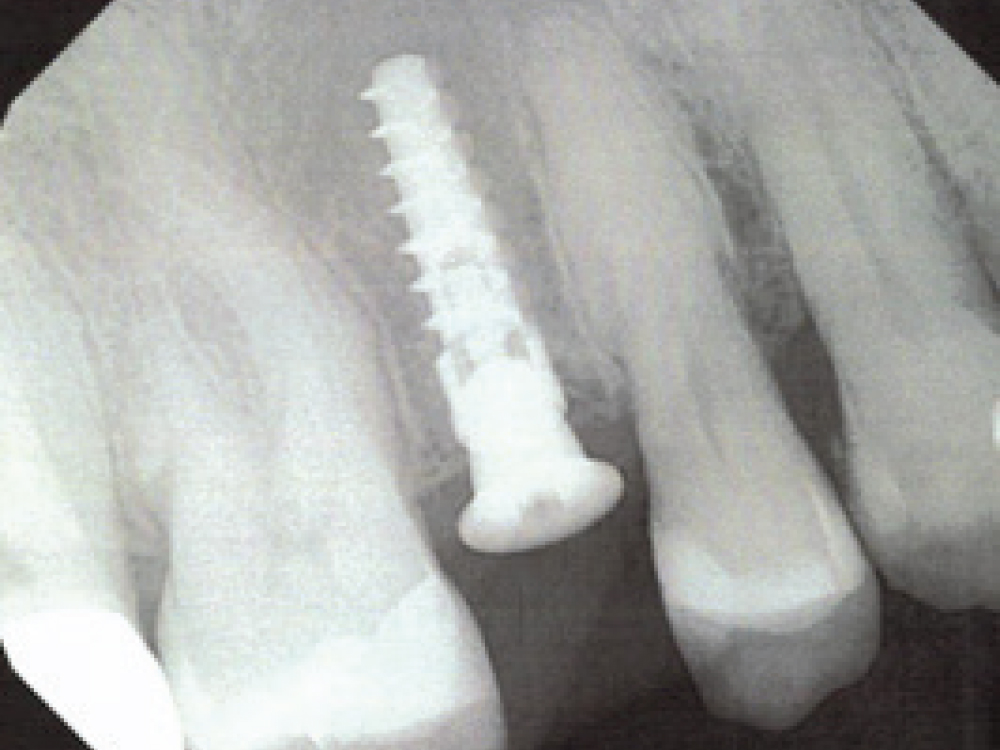

Hahn Tapered Implant Visual

Provided that sufficient primary stability and proper positioning can be achieved, placing an implant during the same appointment the defect is grafted reduces the number of surgical appointments. Here, a Hahn Tapered Implant was placed freehand into an extraction socket with a bony defect. The sharp, pronounced threads of the implant helped keep the implant engaged with the lingual bone, which is essential in avoiding any further damage to the buccal plate. After positioning a Newport Biologics™ Resorbable Collagen Membrane 4–6 (Glidewell Direct), the gaps between the bone and implant were filled with allograft. The surface of the buccal plate was also grafted prior to suturing.

Selecting an implant with an aggressive thread design, like the Hahn™ Tapered Implant (Glidewell Direct), can help prevent the implant from being “bumped” toward the buccal during insertion. The Hahn implant also excels in these situations because the thread design and tapered shape maximize primary stability, and the machined collar and platform-switching nature of the prosthetic connection decrease bone loss.